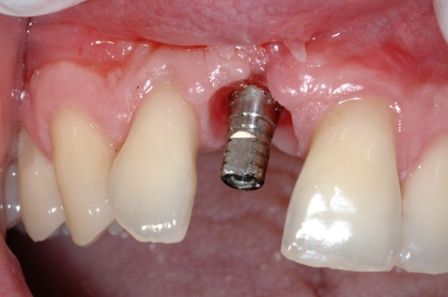

Endosteal implantlar - bu implantlar, cerrahi yöntemle, çene kemiğine direkt olarak implante edilirler. Çevredeki dişeti dokusu iyileştikten sonra, orijinal implanta bağlantı sağlayacak materyali takmak için ikinci bir operasyon gerekir. Son olarak, yapay diş (veya dişler) tek başına veya köprü ya da protez üzerinde grup halinde implanta takılır.

İMPLANTLARIN YERLEŞTİRMESİ VE PROTEZ KADAR SÜRER? Cerrahi işlemin süresi yerleştirilecek implant sayısına ve hastanın koşullarına bağlı olarak yarım saat ile birkaç saat arasında değişebilir. Operasyondan sonra, implant ile kemiğin kaynaşması için (osseointegrasyon) 2-3 ay kadar beklenir. Daha sonra bu implantlar üzerine, birkaç seans süren bir uygulama ile protezler yerleştirilir. İmplantlar dişler çekildikten hemen sonra yerleştirilebilir mi? Evet,günümüzde bu mümkündür.İmplant diş çekimini takiben taze çekim boşluğu içerisine yerleştirilebilir.Buna “immediyat uygulama” denir.